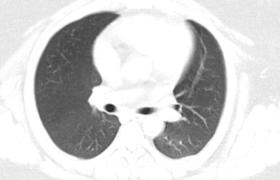

复查CT结果提示双肺可见散在淡薄斑片状磨玻璃密度影,较前无进展(图2-3-66)。连续2次新型冠状病毒核酸检测阴性,符合出院标准,予办理出院。抗病毒药物疗程已足,予停用。

图2-3-66 2020年2月29日胸部CT